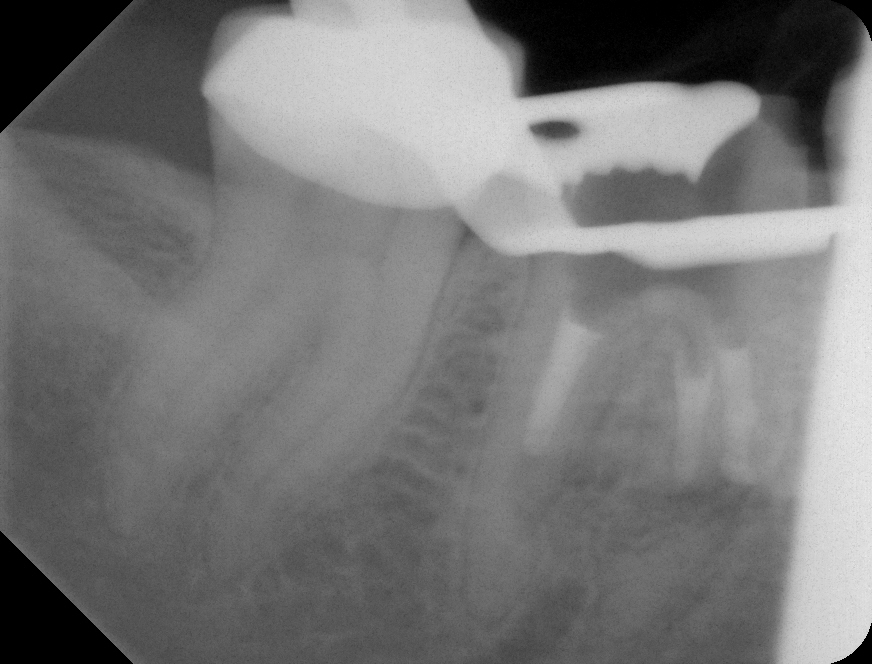

07 – Zahn 46 – WF mit MTA – exzentrisch Veröffentlicht 2. Juli 2013 am 872 × 664 in Wurzelresorption mal anders